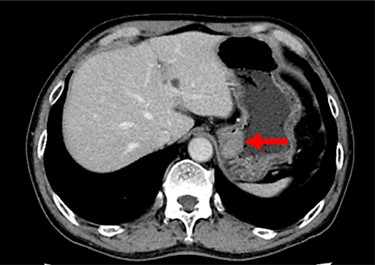

A 74-year-old man presented to the hospital for follow-up esophagogastroduodenoscopy (EGD) after Helicobacter pylori eradication. EGD revealed a large necrotic ulcerated mass at the cardia of the stomach (Fig. 1). Endoscopic biopsy revealed a malignant tumor negative for cytokeratin AE1/AE3, CD45, chromogranin A and synaptophysin on immunohistochemical (IHC) staining, and initial diagnosis was poorly differentiated adenocarcinoma. Physical examination, routine blood investigations and serum tumor marker levels, including carcinoembryonic antigen, CA-125 and CA 19-9, were normal. Abdominal computed tomography (CT) showed thickness of the stomach wall directly below the esophagus (Fig. 2, red arrow). Enlarged lymph nodes and distant metastatic lesions were absent. Radical surgery including total gastrectomy and D2 lymph node dissection was performed. Surgical specimens demonstrated a whitish amelanotic mass with central ulceration, present at EGJ, measuring 38 mm × 30 mm and protruding into the gastric lumen (Fig. 3A). Histological examination revealed polygonal and round neoplastic cells with round nuclei and prominent nucleoli nestled within the esophageal squamous epithelium, thus forming an ‘in situ’ lesion. No melanin deposition was found in the neoplastic cells. Immunohistochemically, neoplastic cells were positive for HMB45 and S-100 (melanoma markers; Fig. 3B–D). The final diagnosis was primary amelanotic malignant melanoma of esophagus, T2, N0 and M0 (UICC [International Union against Cancer] classification system, 7th ed.). Four months after surgery, abdominal CT revealed multiple liver metastases. The patient received seven cycles of nivolumab monotherapy, with two subsequent cycles of nivolumab and ipilimumab. Liver metastases were initially controlled by immunotherapy, but they eventually worsened, as assessed by the Response Evaluation Criteria in Solid Tumors ver. 1.1 (Fig. 4).

Contrast-enhanced CT showing progression of multiple cystic metastases in the liver.